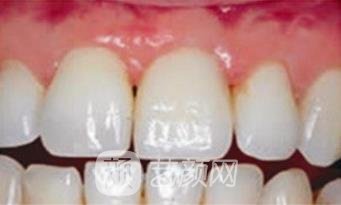

二、苏州相城口腔医院种植牙案例

怀着忐忑的心情来到了医院,让医生帮我看了看牙齿的问题,医生建议我将龋坏的牙齿拔掉,重新做个种植,我也听从了医生的专业意见,很快医生就帮我安排了手术,种植牙齿的过程中没有出现任何不良的情况,手术很顺利的就做完了,做完手术之后开始不太适应,经过了一段时间的磨合,牙齿用着就顺利多了,跟我自己的牙没太大区别,正常的咬合和咀嚼功能都挺好的。